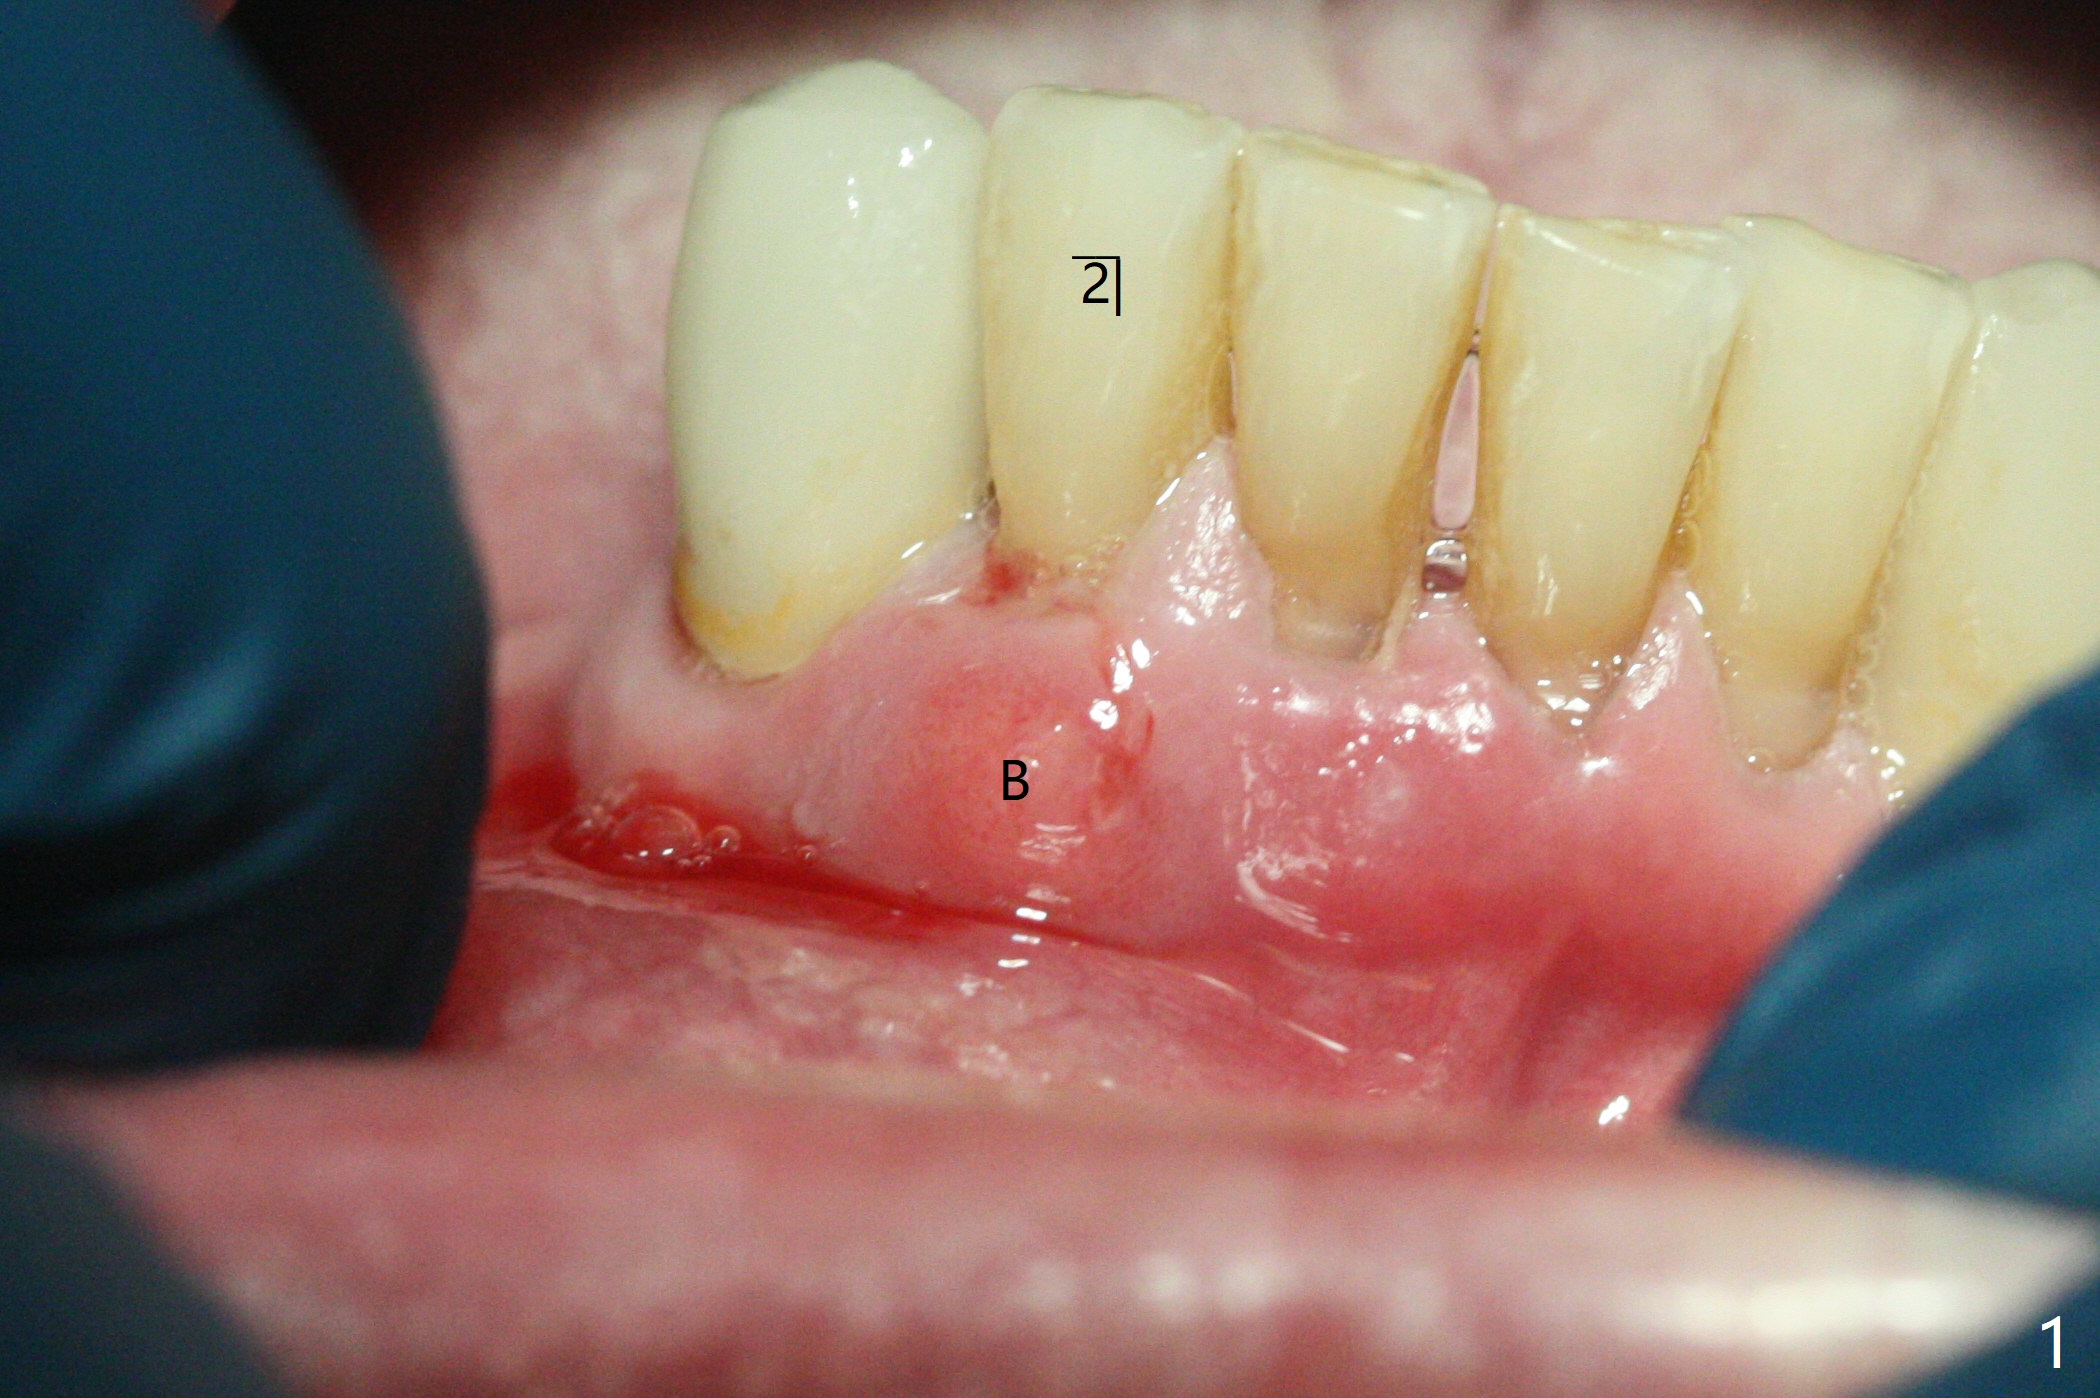

70岁男有上颌全口义齿,下颌局部义齿,后者由于右下切牙肿痛,松动无法戴入(图一至三),左下1骨质吸收严重,但是没有症状(图四)。理想治疗拔除右下1,2,即刻植牙,预防右下三断裂,不过病人没有思想准备,同意即刻植骨(图五,6个月吸收膜)。右下1舌侧,2颊侧脓肿(图一,二),拔牙时发现相应骨质缺损严重。四个月后在右下2植牙,做悬臂桥。当左下1不行时,做单个植牙,这样病人至少可以暂时使用局部托牙。